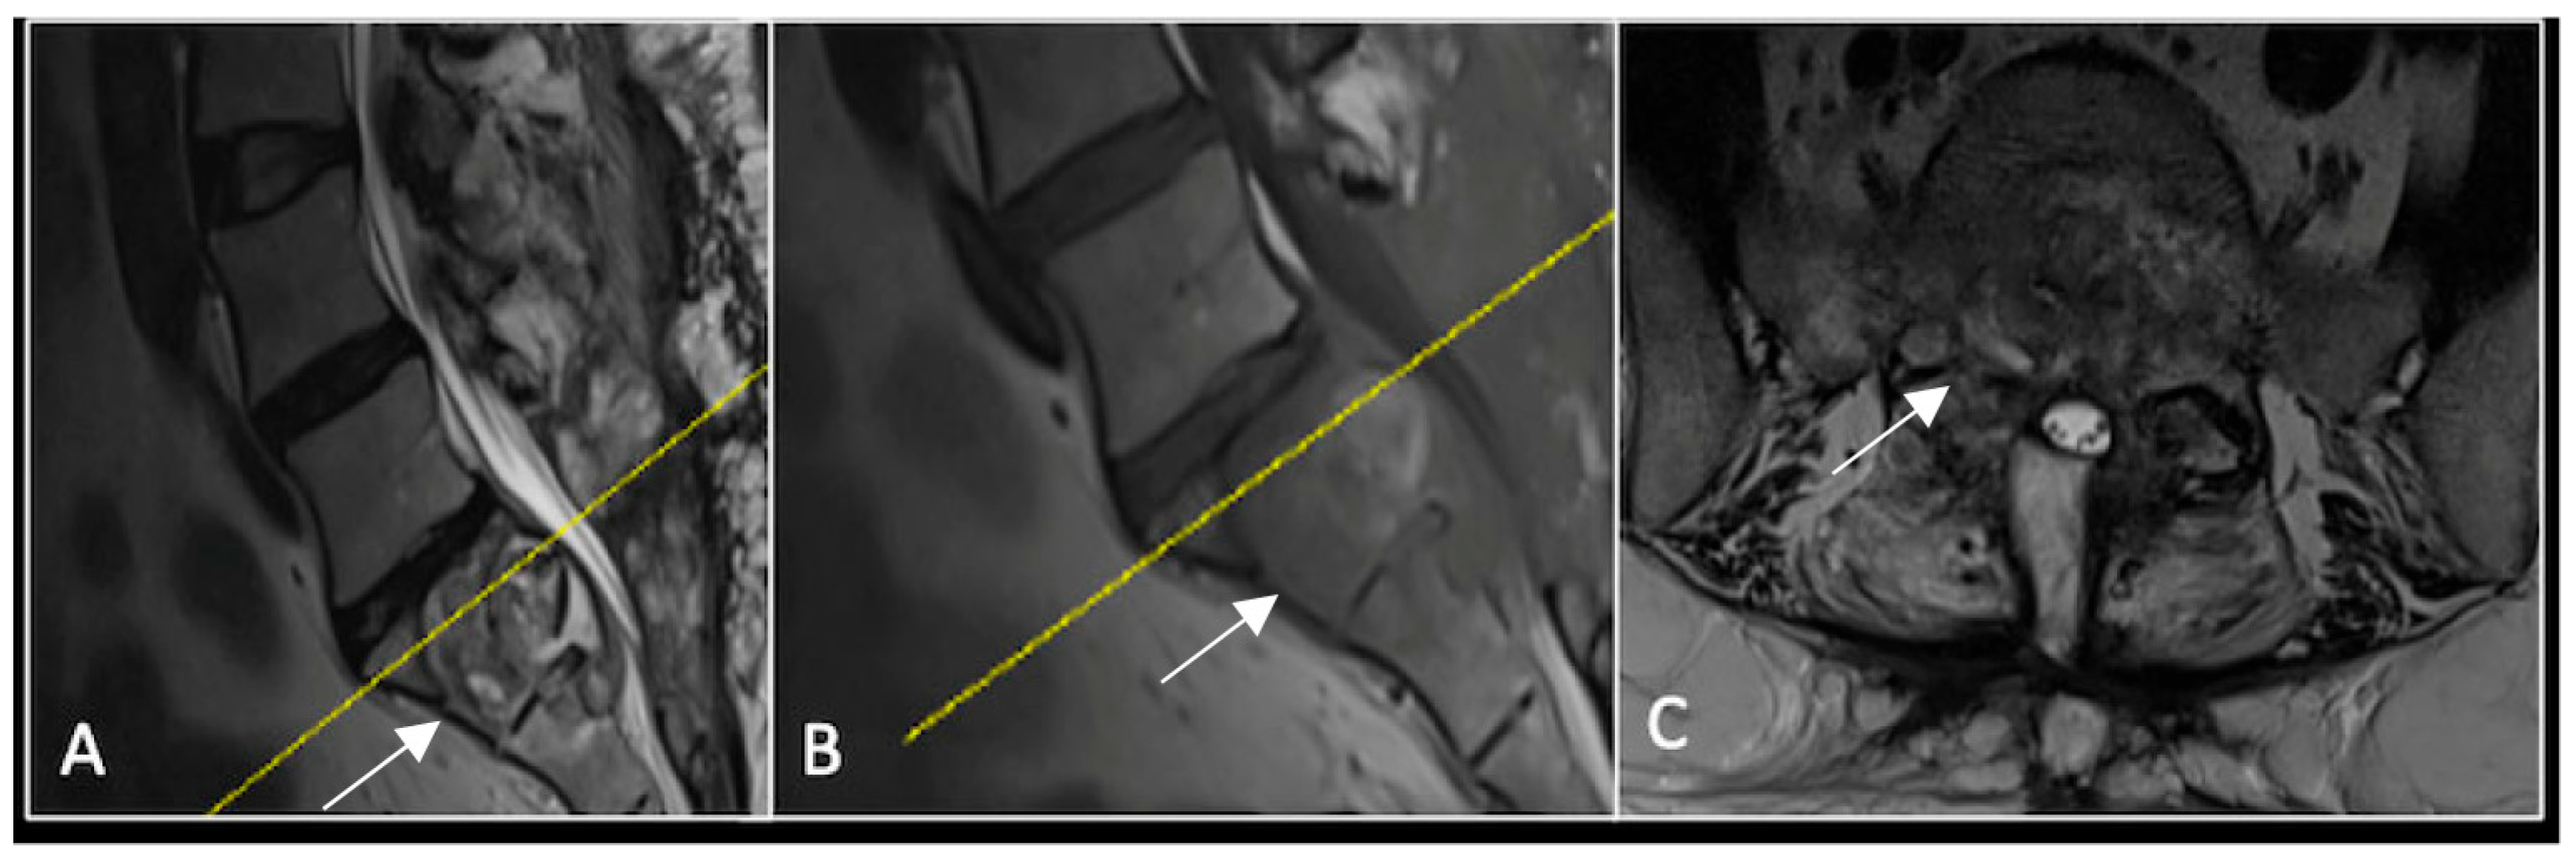

This 63-year-old male presented with sacral pain and right-sided S1 radiculopathy. He was subsequently referred to our institution after diagnostic imaging revealed a destructive lesion within the S1 vertebra (Figure 4). The patient developed symptoms of acute cauda equina syndrome, for which we recommended an emergent surgical decompression to be performed at the referring hospital. Biopsy confirmed a conventional chordoma. The patient chose to undergo separation surgery, given the significant morbidity associated with an en-bloc sacral resection, including sacrifice of the neural structures innervating his bladder and bowel. He received adjuvant proton beam therapy, and 6-monthly surveillance imaging revealed stable disease (Figure 5). Unfortunately, 12 months post-separation surgery, there was evidence of tumour progression with epidural extension and symptomatic deterioration in bladder function, requiring revision surgical debulking (Figure 6).

Figure 6.

MRI imaging following revision debulking surgery. (A) T2W sagittal; (B) T1W sagittal; (C) T2-weighted axial. Imaging shows an air cavity within the S1 vertebral body where tumour has been resected and fluid within the epidural space that is displacing the thecal sac posteriorly. The yellow line on the sagittal images denotes the level corresponding to the axial section.